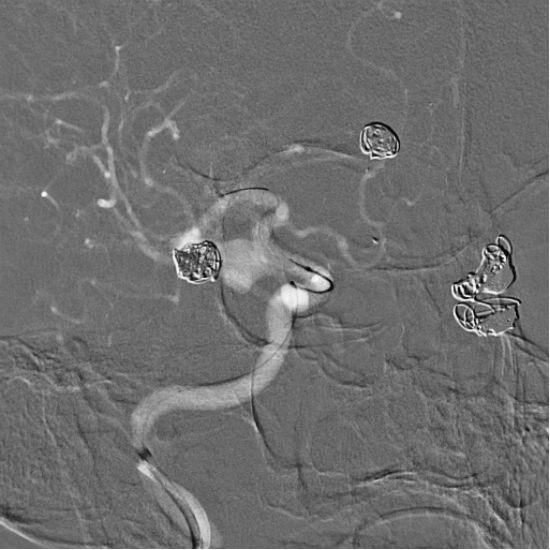

Preoperative angiography revealed a shared trunk of bilateral anterior cerebral arteries, with a saccular aneurysm (8 mm × 6 mm) on the left anterior cerebral artery, a recurrent aneurysm (9 mm × 5 mm) on the left middle cerebral artery, and a wide-neck aneurysm (8 mm × 8 mm) on the right posterior communicating artery.

3D imaging of the left internal carotid artery

Anterior-Posterior view of the left internal carotid artery

Angiography of the right internal carotid artery